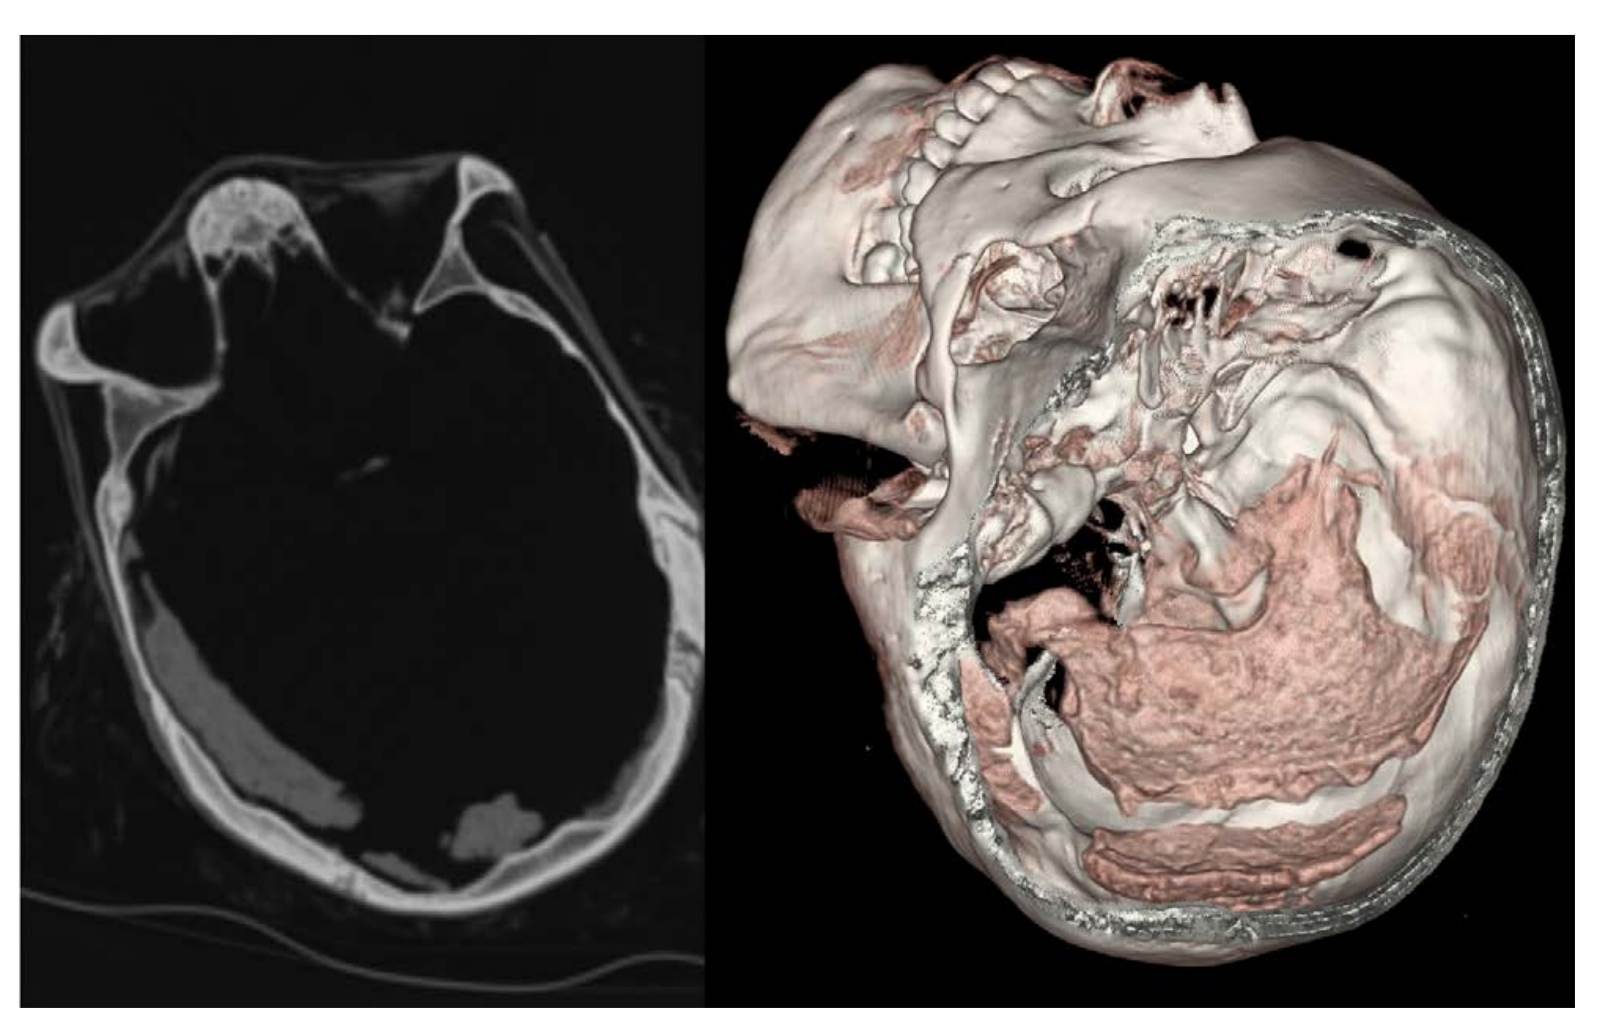

| Fotografía de la momia guanche del MAN comparada con reconstrucciones 3D realizadas en el TC la misma posición. (Fuente: MAN. Autor HUQS) |